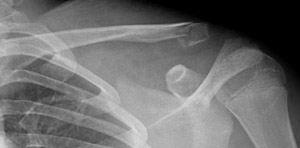

релом Ключицы У Ребенка Фото

Перелом Ключицы У Ребенка Фото 111 фотографий